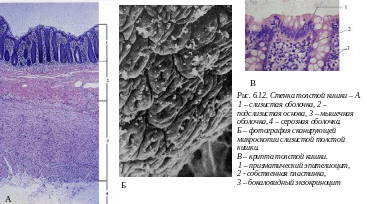

6.2.5. Микроскопическое строение и функциональные особенности толстого кишечника

Толстый кишечник представлен слепой кишкой, червеобразным отростком, восходящей ободочной, поперечно-ободочной, нисходящей ободочной сигмовидной и прямой кишкой. В толстом кишечнике происходит формирование каловых масс, всасывание воды. В секрете толстой кишки много слизи, но важных ферментов не вырабатывается, хотя пищеварение продолжается за счет ферментов тонкой кишки и ферментов микрофлоры кишечника.

Слизистая оболочка толстой кишки имеет следующие особенности строения:

-

Отсутствуют ворсинки.

Складок и крипт значительно больше, чем в тонком кишечнике.

Просвет крипт значительно шире; они состоят из каемчатых, недифференцированных клеток, большого количества бокаловидных клеток и эндокриноцитов. Клетки Панета отсутствуют.